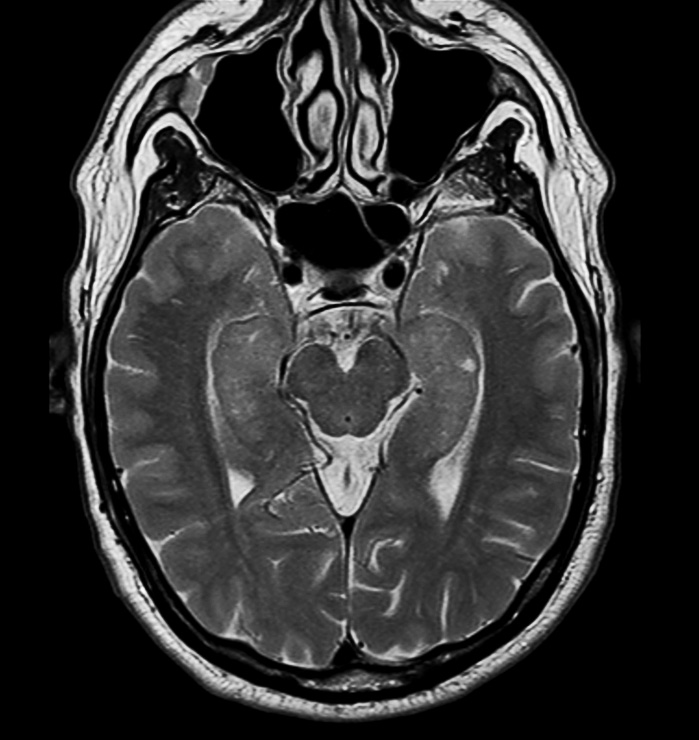

Hippocampus